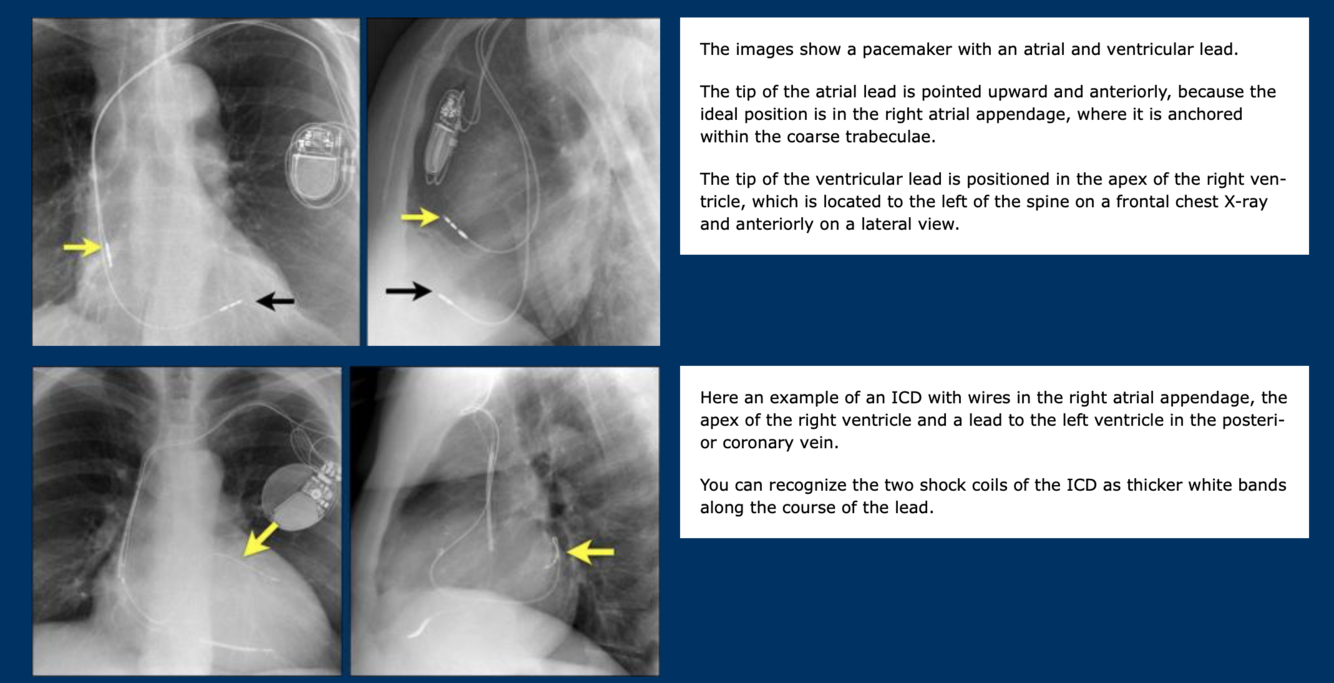

What devices are imaged?

Where are the leads placed?

1 PPM

2: Implantable cardioverter-defibrillator (ICD)